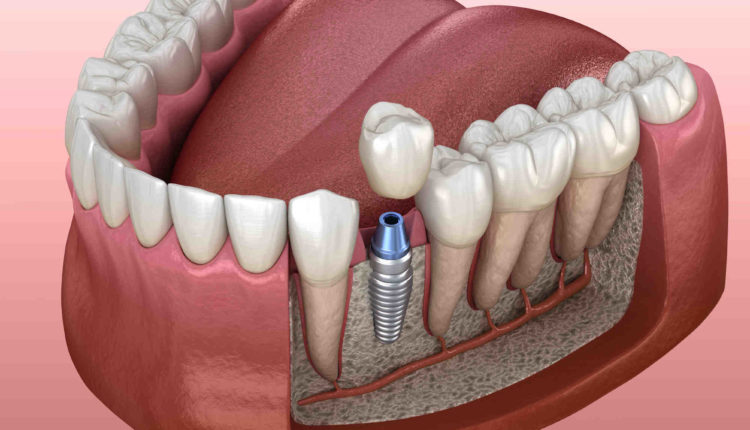

A periodontist is a dentist who specializes in the prevention, diagnosis, and treatment of periodontal disease, and the placement of dental implants. Periodontists are also experts in the treatment of oral inflammation.